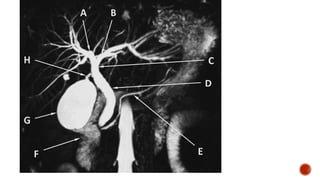

PORTAL VENOUS SYSTEM

 The major vessel of the portal system is the portal vein.

 The portal vein is formed by the union of the splenic vein and the